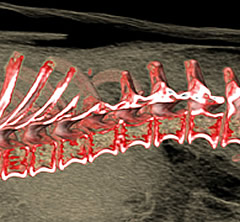

前腕骨骨折整復

前腕骨(橈尺骨)遠位骨折

整形外科領域でも癒合不全や癒合遅延といった骨の治癒過程でのトラブルが非常に多い部位です。

術後:前腕骨骨折整復

プレートとスクリューを使用した強固な内固定術を実施。